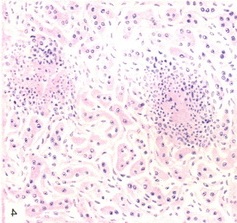

![]() Рис. 9. Гидропическая дистрофія печінки. Різко набряклі гепатоцити зі світлою цитоплазмою і центрально розташованим ядром - балонні клітини. |

Гидропическая дистрофія - наростання процесів, властивих мутному набухання, з різким збільшенням води в цитоплазмі. Вода накопичується спочатку в индоплазматическом ретикулумі, потім в решті цитоплазмі. Мікроскопічно в гепатоцитах розріджена цитоплазма, ядро розташована центрально, добре окреслені контури клітин. Частина гепатоцитів, переважно в центрі часточок, перетворюється в балонні клітини (рис. 9). Нерідкі пікноз і кариолиз ядер і некроз балонних клітин. Гидропическая дистрофія, наявність балонних клітин характерні для епідемічного гепатиту.